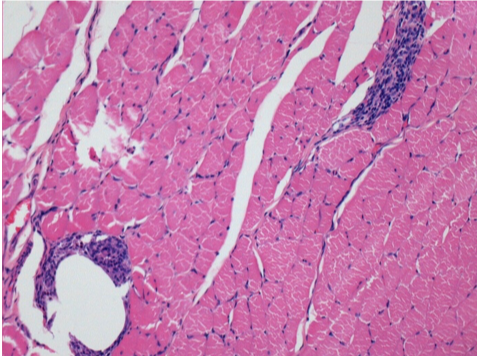

3 months (D90)after Endopeel Injection 0.1ml in the right pretibial muscle.